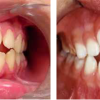

Turritavad ülemised lõikehambad

Ülemised eesmised hambad võivad olla liigselt ettepoole kaldunud mitmel põhjusel. - Hammaste huule poole kaldumine võib olla funktsionaalne ehk tingitud valedest harjumustest (suuhingamine, infantiilne neelamine), - kahjulikest harjumustest (pöidla, sõrme,...